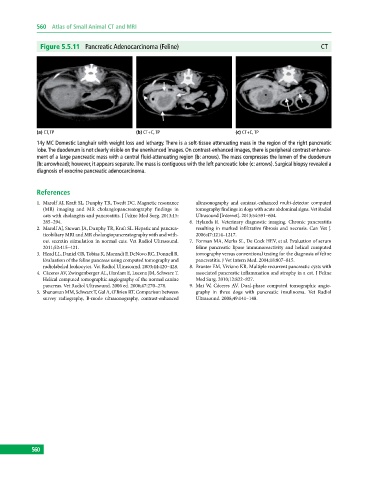

Figure 5.5.11 Pancreatic Adenocarcinoma (Feline) CT

(a) CT, TP (b) CT+C, TP (c) CT+C, TP

14y MC Domestic Longhair with weight loss and lethargy. There is a soft‐tissue attenuating mass in the region of the right pancreatic

lobe. The duodenum is not clearly visible on the unenhanced images. On contrast‐enhanced images, there is peripheral contrast enhance-

ment of a large pancreatic mass with a central fluid‐attenuating region (b: arrows). The mass compresses the lumen of the duodenum

(b: arrowhead); however, it appears separate. The mass is contiguous with the left pancreatic lobe (c: arrows). Surgical biopsy revealed a

diagnosis of exocrine pancreatic adenocarcinoma.